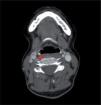

Figura 2.

Quatro ramos do arco aórtico: 1: tronco braquicefálico; 2: artéria carótida comum esquerda; 3: artéria vertebral esquerda; 4: artéria subclávia esquerda.